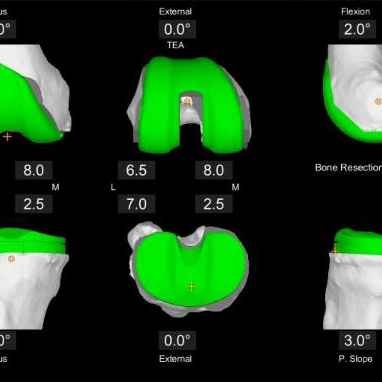

Dank CT-basierter 3D-Planung und der einzigartigen AccuStop™-Technologie ermöglicht der Stryker Mako-Roboter minimalinvasive Eingriffe, bei denen gesundes Gewebe optimal geschont und das Implantat millimetergenau positioniert wird.